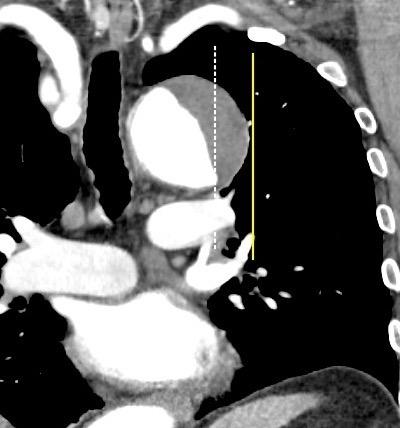

53. BPI .COMPRESIÓN Y DESPLAZAMIENTO HACIA ARRIBA DEL

55. BPI . COMPRESIÓN Y DESPLAZAMIENTO HACIA ABAJO DEL